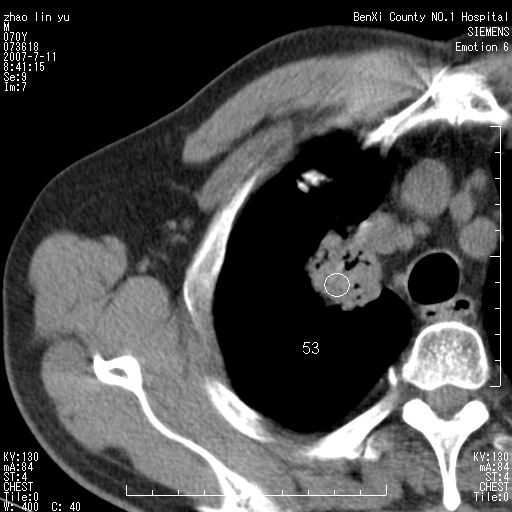

以下是引用王靖旗在2007-7-10 17:12:00的发言:[br] 男、70、咳嗽两个月,半年前换瓣手术,胸片未见异常,于昨天行x片发现右肺上野大片影,行ct扫描,这里是减薄图像,余肺正常。明天晚上会有增强扫描片,到时我会上传。[br][br] 冠状位请大家细看,应该是有意义的,[br][br] 请大家先看平扫发表意见。[br][br]